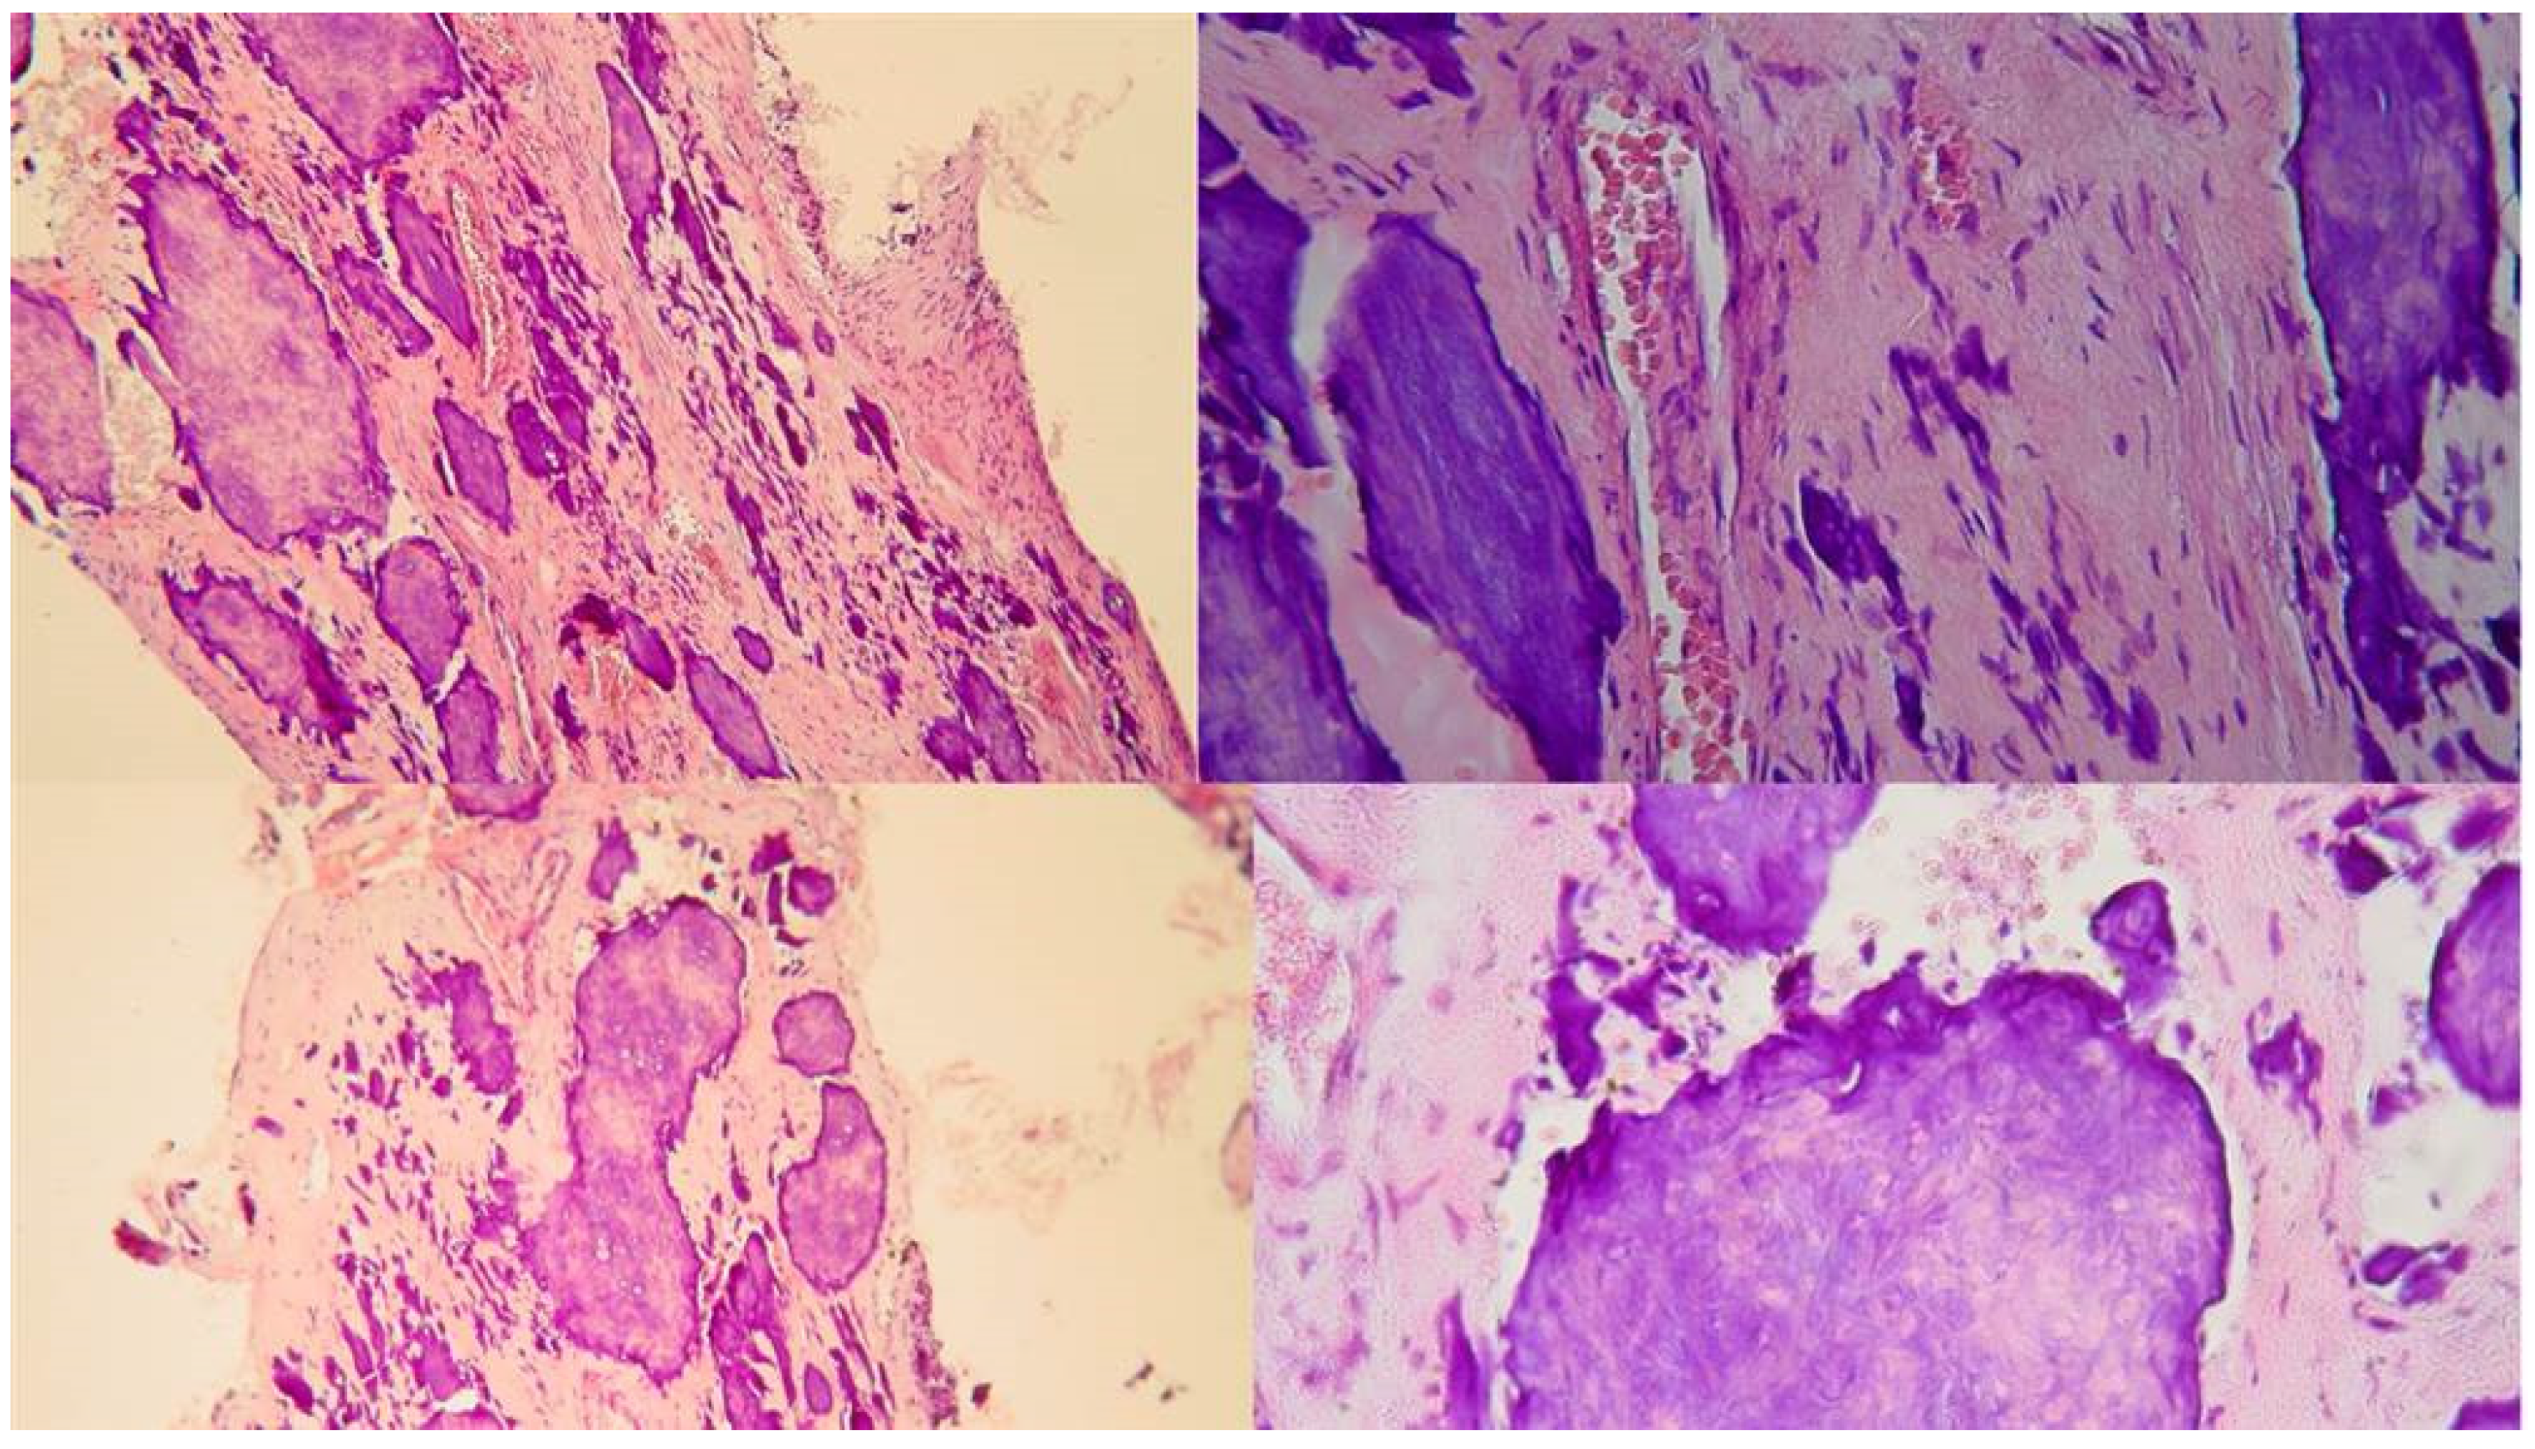

Figure 3.

Histological images of the calcified vital pulp tissue that was removed during the root canal treatment of a second mandibular molar with deep periodontal distal lesion suffering from symptomatic irreversible pulpitis. Notice the linear calcified nodules formed along the root pulp vessels. (hematoxylin eosin staining) (Histological images courtesy of prof. Domenico Ricucci).

Figure 5.

The free pulp stone's histology shows distinct calcified nodules growing around a network of unmineralized extracellular matrix material and capillary vessels. (hematoxylin-eosin staining).

Two distinct types of pulp calcification have been suggested to exist (Goga, 2008): diffuse or linear calcifications predominantly found in the radicular pulp (

Figure 3) and pulp stones (denticles) more common in the coronal region (

Figure 4 and

Figure 5).

The denticles, classified as true or false based on structure, exhibit morphological distinctions rather than chemical differences. True denticles resemble dentin with dentinal tubules, odontoblastic processes, and few odontoblasts, while false denticles consist of concentric layers of calcified tissue surrounding a central cellular area, which may be necrotic and act as a nidus for denticle formation. Based on location, denticles are categorized as embedded, interstitial, adherent, or free (Goga et al., 2008).

Moreover, diffuse Calcifications are usually formed as amorphous unorganized linear columns lying parallel to the blood vessels of the pulp and they are like the calcifications seen in other tissues of the body following degeneration (calcific degeneration) (

Figure 3). Fibrillar calcifications are one of the manifestations of the regressive changes that the pulp undergoes. The incidence of pulp calcifications seems to be relatively high, especially based on microscopic examination because many of the calcifications are not of sufficient size to be discernible in radiographs. Calcifications seem to increase with age, with about 90% of those of 50 yr or older being reported as affected. As teeth age, vascular, lymphatic, and nerve supplies decline, and fibroblasts decrease in size and number (Maeda 2020). A reduction of 15.6% in crown odontoblasts, a reduction of 40.6% in root odontoblasts, and a decreased secretory activity have been observed, suggesting that the reparative capacity of the pulp is compromised with aging. The age-related changes include increases in cross-linkages and the number of collagen fibers, lipid infiltration, and calcifications. Despite many studies having investigated the mechanisms underlying these age-related changes, we still have much to learn about the biological control mechanisms responsible for cellular activity and survival throughout life. The mechanism of hard tissue formation during CM is not yet clear. Several hypotheses have been proposed to explain this phenomenon. Torneck (1990) hypothesized that the deposition of hard tissue is either because of stimulation of the pre-existing odontoblasts or by loss of their regulatory mechanism. On the other hand, Andreasen et al. (1987) described CM as a response to severe injury to the neurovascular supply to the pulp, which after healing leads to accelerated dentin deposition and is closely related to the loss and re-establishment of the pulpal neural supply. Neither mechanism has been proven or studied, and further investigation is required to provide an evidence-based understanding of this occurrence. Calcific metamorphosis is characterized by osteoid-like tissue that is produced by the odontoblasts at the periphery of the pulp space or can be produced by undifferentiated pulpal cells that undergo differentiation because of the traumatic injury (Amir at al. 2001, Pissiotis et al. 2007). This results in a simultaneous deposition of dentin-like tissue along the periphery of the pulp space (root canal walls) and within the pulp space proper (root canal). These tissues can eventually fuse, producing the radiographic appearance of a root canal space that has become rapidly and completely calcified (Paterson & Mitchell 1965). Clinically, there is usually a clear distinction between the calcified irregular tissue and the peripherical dentinal walls reflecting the different histological characteristics and mechanisms of formation of the tissues obliterating the pulp space. Under the magnification and illumination provided by a dental operating microscope, these tissues reflect the light in different ways. Usually, when searching to negotiate a calcified canal under the dental operating microscope the operator evaluates the different dentine colors and textures on the axial view plane. In a single-rooted calcified tooth, the concentric axial orientation of the dentinal tubules is visible under the microscope giving a concentric radial appearance (